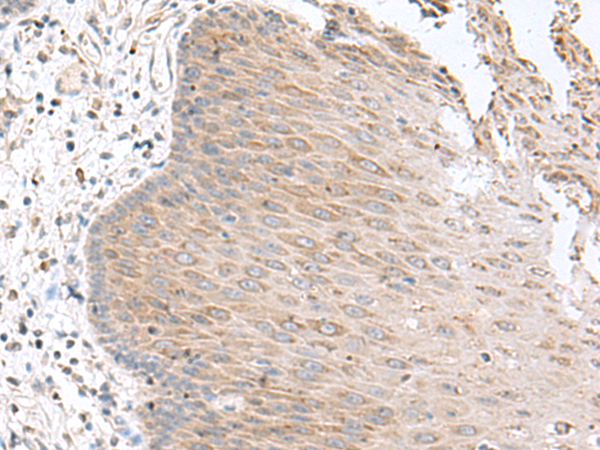

分类: 科研抗体货号: P11000别名: MDS, LIS1, LIS2, MDCR, PAFAH应用: IHC反应种属: Human, Mouse, Rat